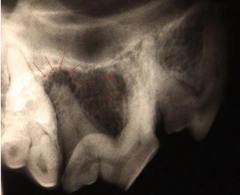

Eigentlich sollte bei diesem Hund eine Zahnprophylaxe durchgeführt werden. Bei der jährlichen Routineuntersuchung war vermehrte Zahnsteinbildung - besonders auf der rechten Seite - aufgefallen. Nach gründlicher Reinigung in Narkose fiel uns am Reißzahn im rechten Oberkiefer ein kleines Loch auf, das sich unter dem Zahnstein versteckt hatte. Im Röntgenbild erkennt man, dass die Wurzel angegriffen ist: durch das Loch konnten Keime aus der Maulhöhle in den Wurzelkanal eindringen. Die kleinen Pfeile weisen auf den entzündeten Knochen am Zahnfach. Dies ist die Erklärung für die vermehrte Zahnsteinbildung auf der rechten Seite: die Entzündung verursacht Zahnschmerzen und der Hund vermeidet es, auf dieser Seite zu kauen. Der entzündete Zahn wurde gezogen - die Entzündung heilt unter Antibiose und Schmerztherapie nach ein paar Tagen ab.

Fazit: auch ein noch so unscheinbares Loch im Zahn kann große Schmerzen verursachen - da unsere Vierbeiner im wahrsten Sinne des Wortes "die Zähne zusammenbeißen" und nicht mit uns sprechen, werden wir häufig von schwerwiegenden Befunden überrascht. Mancher Mensch hätte mit so einer Wurzelentzündung gar nicht mehr "gefressen" und sehr offensichtlich gelitten...